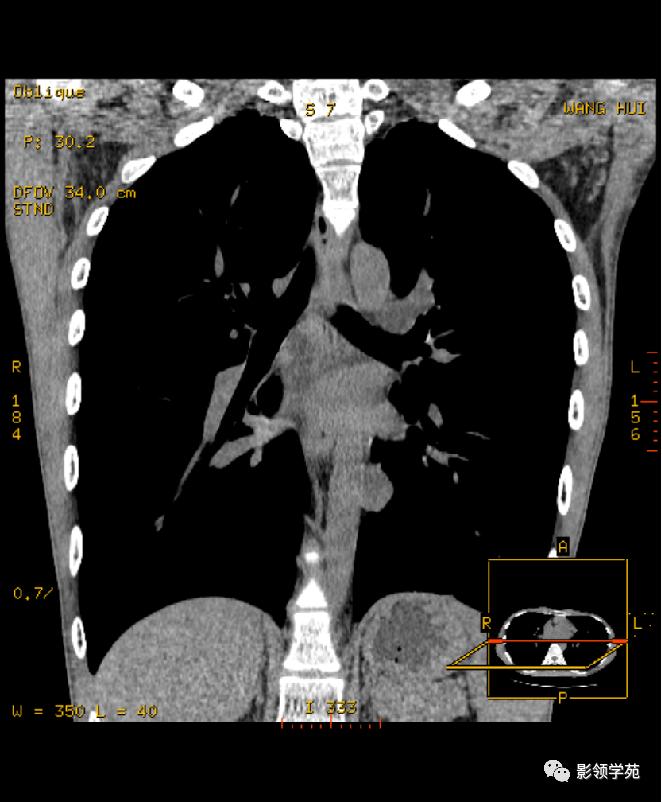

多发性骨髓瘤病例:右侧心膈角囊性肿块,与心包紧密相连

上图为第一次检查图像,下图为复查图像,囊性灶明显缩小